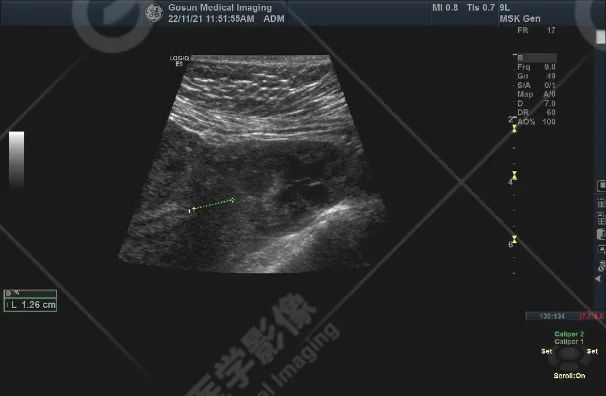

前位子宫,包膜光滑完整,形态饱满,实质回声不均匀增粗,内膜前移、清晰,厚约 15 mm;左侧宫角可见一向外突起的混合回声团块,大小约 34 mm×27 mm,边界欠清,形态尚规则,内部可见多处大小不等的无回声区,内侧与宫腔不相通,外侧肌层不完整,局部仅可见浆膜层,CDFI 显示其内可见丰富血流信号,PW 显示内部 Vp = 45 cm/s,RI = 0.23。

左侧宫角旁混合性包块 (考虑左输卵管间质部妊娠);子宫腺肌病;双侧卵巢未见明显异常。